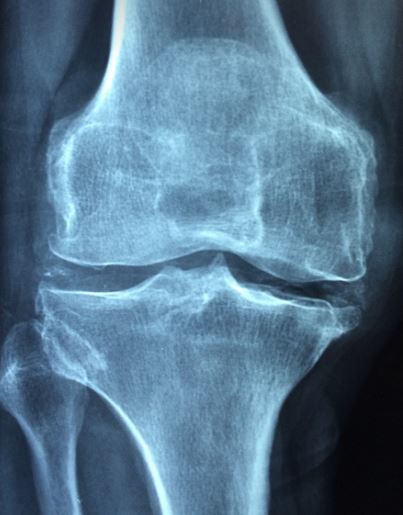

4. 무릎줄기세포주사 실비 및 실손보상 대상 및 조건 무릎줄기세포주사 대상 및 조건 보건복지부에서 정한 무릎줄기세포 치료 대상은 두 가지 중에 하나에 해당이 되어야 합니다. 또한 무릎줄기세포주사는 '신의료기술'로써 건강보험법상 법정비급여 항목이기 때문에 실손보험으로 보상이 되고 있습니다. 관련내용을 확인해 보시죠. 1. 무릎줄기세포주사 보건복지부 고시 기준 - ICRS 3~4등급은 무릎연골의 손상 정도가 50% 이상이어야 보건복지부에서 고시한 치료대상으로 인정이 됩니다. 이것이 등급으로 봤을 때 ICRS 3~4등급에 해당되어 치료대상입니다.

- KL 2~3등급은 관절의 간격이 정상인 분들과 비교했을 때 확연히 좁거나 변형이 온 환자고 치료 대상에 해당됩니다.

무릎줄기세포주사 3~4등급 2. 실손보상 적용가능 상품기준 - 2009년 9월 이전의 가입자(1세대)와 2017년 9월 이전의 가입자(2세대)의 경우에는 연간 한도까지 보상이 된다고 합니다.

무릎줄기세포주사치료를 실손보상과 함께 진행하시려면 본인이 치료대상인지 확인하시고 진행하는 것이 바람직하니 치료 전 반드시 병원 내 검사를 통하여 대상에 해당여부를 필히 확인하는 것이 옳습니다. 보험회사에 치료 대상인지 해당여부 확인을 위해 MRI 및 X-ray 검사결과내용을 요구할 수 있으니 치료하시기 전에 검사결과와 의무기록 발급을 꼭 요청하시는 것이 안전합니다. (출처 : 금융감독원 홈페이지)